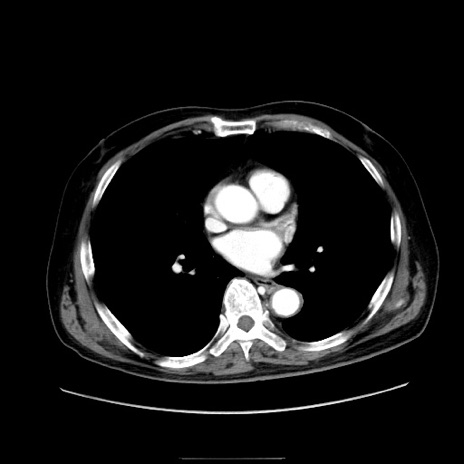

症例30(横断像)

【症例】80歳代男性

【主訴】臍周囲痛

【現病歴】約6時間前から臍下部痛が出現。次第に腹部膨隆・背部痛も生じてきたため来院。背部痛の場所は変化しない。

【既往歴】腎盂腎炎

【身体所見】意識清明、BT 36.3℃、BP  131/87mmHg、P 87bpm、SpO2 100%(RA)、臍周囲自発痛・圧痛あり、反跳痛なし、自発痛部位に一致して板状硬あり、腹部膨隆、腸雑音減弱、CVA tenderness両側陰性。

【データ】WBC 19600、CRP 0.33